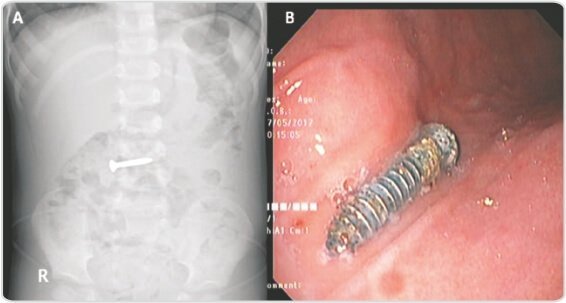

A 3-year-old child presented to us 6 hours after ingestion of a sharp screw.

Abdominal X-Ray revealed the screw in duodenum. On endoscopy, the screw was identified in the second part of duodenum. It was repositioned into the stomach using a snare. Subsequently, it was retrieved following a similar technique and steps after applying glue.